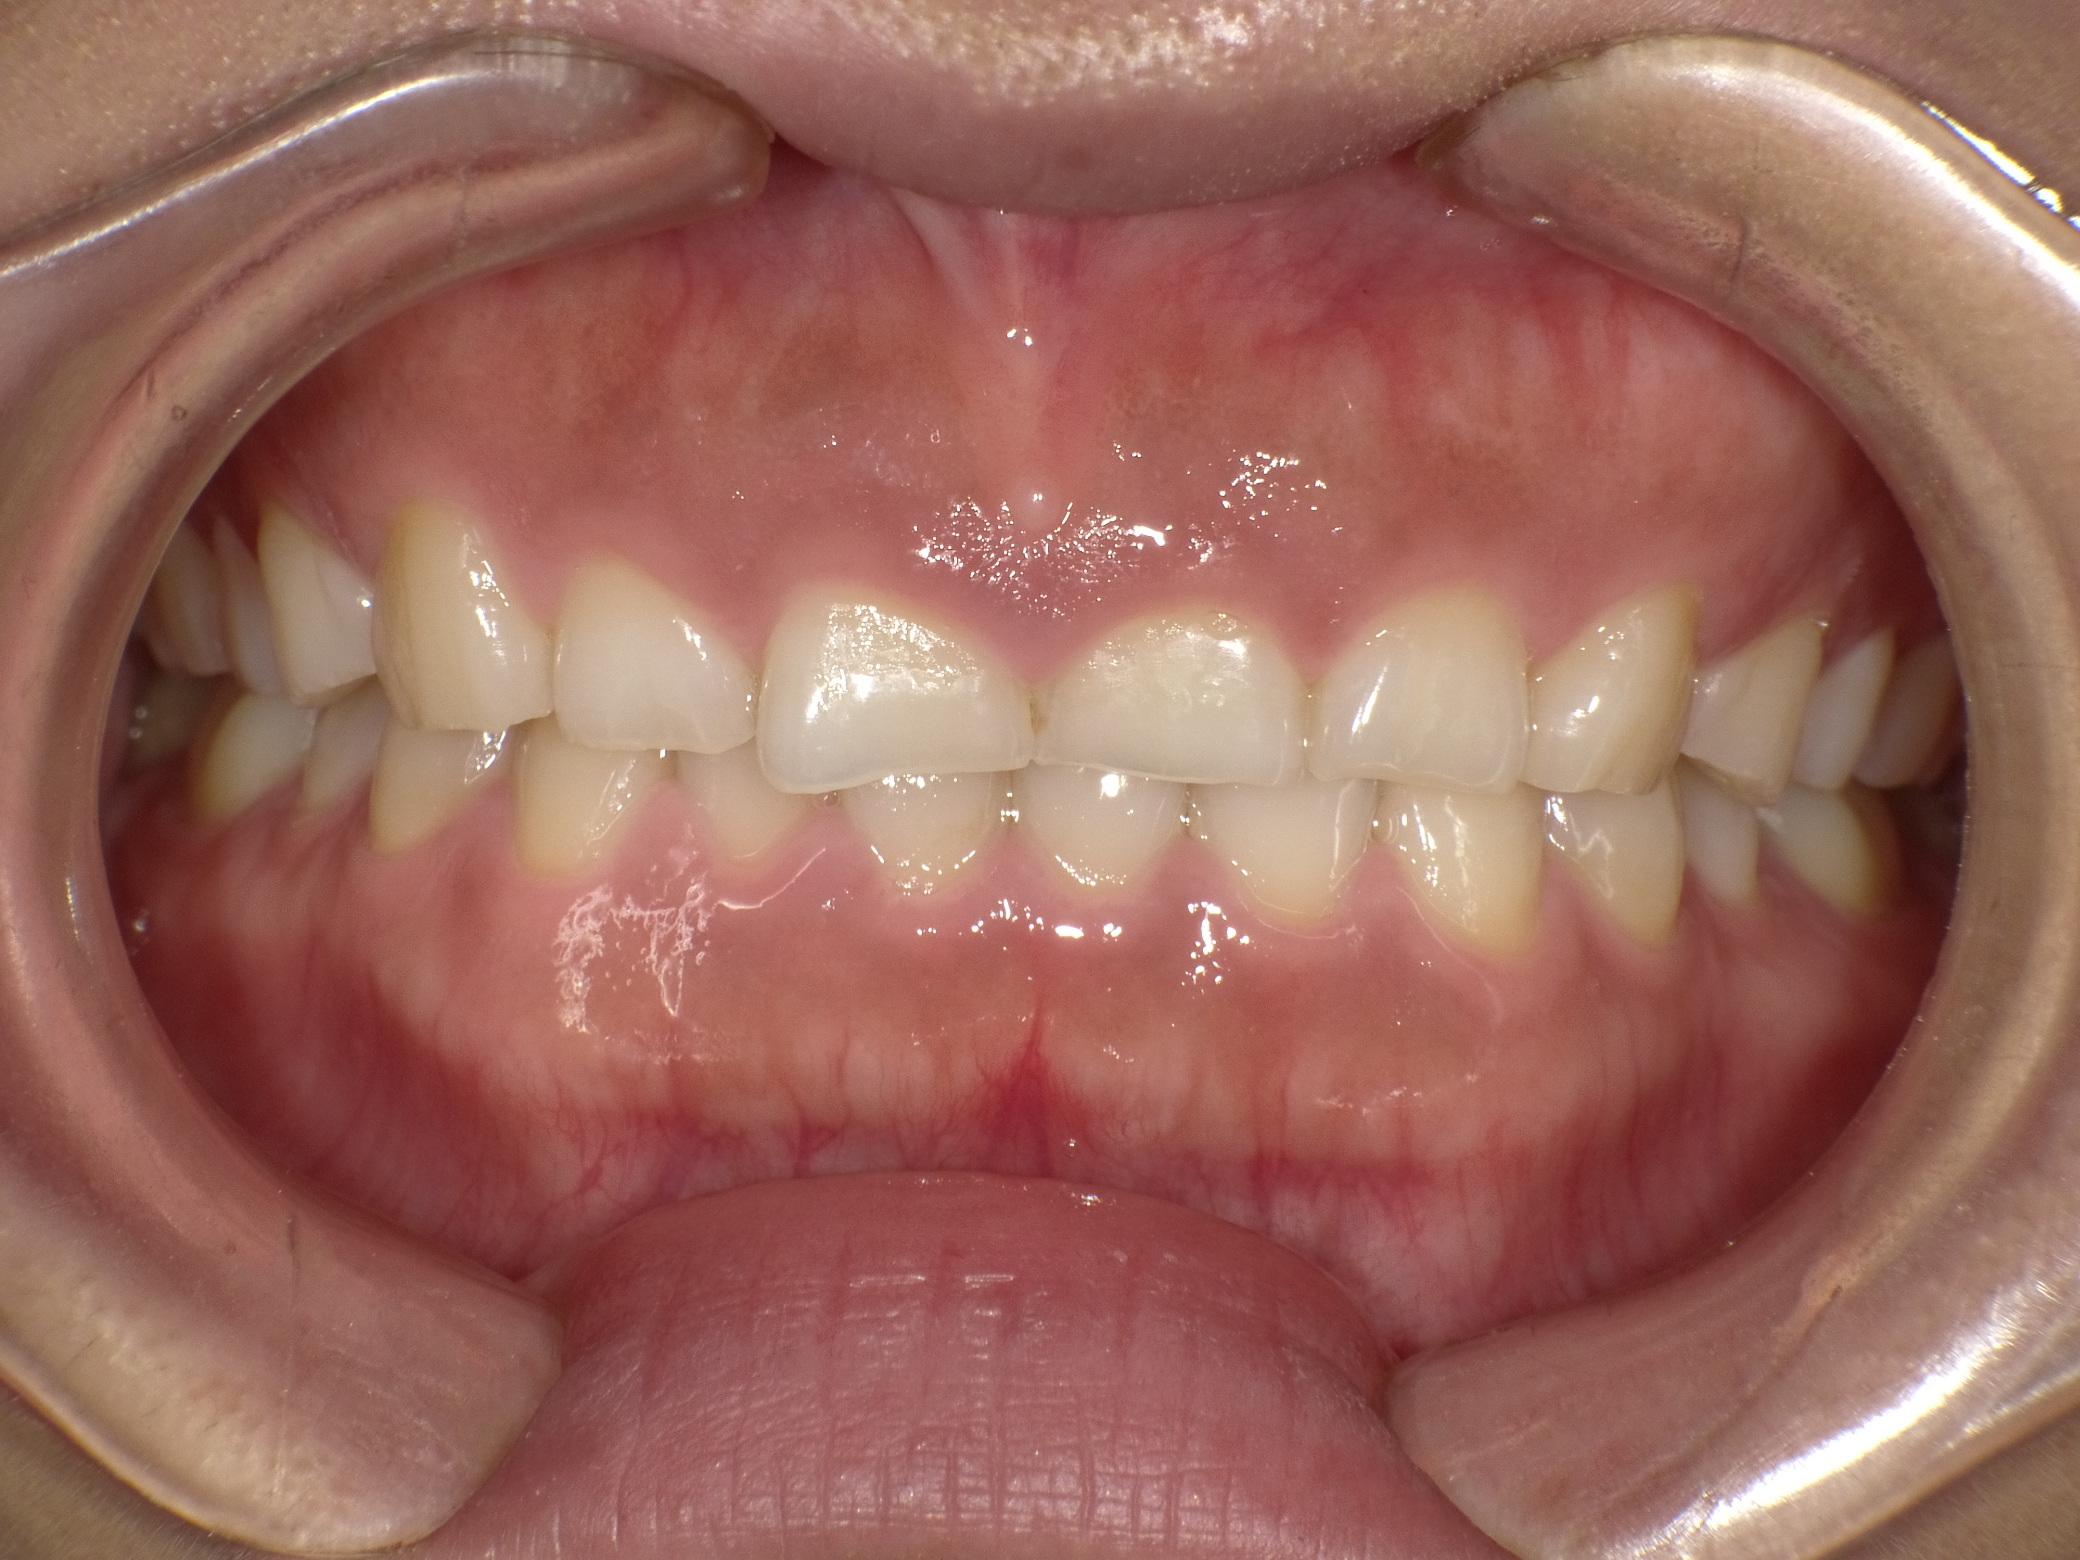

インビザラインやマウスガード矯正による酸蝕に注意

最近10代のインビザラインによる歯並び矯正が多くなっております。 しかし、インビザラインの公...